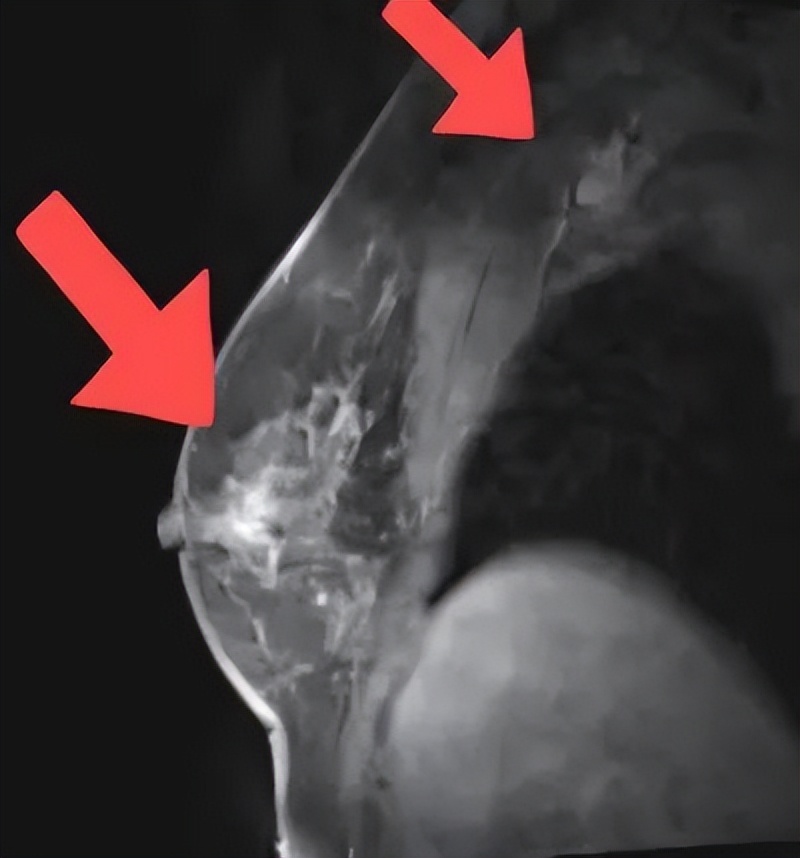

2021年11月29日乳腺MR提示:右侧乳腺异常信号肿物较前缩小,现约2.7*1.6cm,形态不规则,右腋窝淋巴结,较前略缩小,现短径约1.3cm,考虑转移。

2022年1月6日乳腺MR提示:右侧乳腺肿物较前缩小,边界欠清,短径1.1cm,右侧腋窝淋巴结短径约0.8cm。

2022年2月11日乳腺MR提示:右侧乳腺肿物较前进一步缩小,边界欠清,原肿物处现仅见点状强化灶,约0.4cm,右腋窝淋巴结现已不具体。

2021.9.30

2022.1.6

2022.2.11

图2 乳腺核磁

治疗6个周期后,2022.2.11乳腺MR显示靶病灶显著缩小,临床疗效评估为PR。